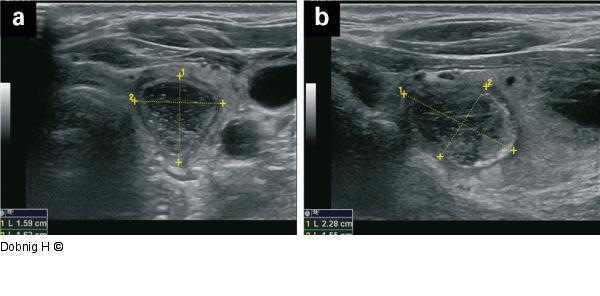

Abbildung 13: Alkoholablation - Schilddrüse Sechs Monate nach der Punktion stellt sich ein kleiner narbiger Rest mit den Ausmaßen 1,6 × 1,6 × 2,3 cm dar, einem Volumen von 2,9 ml entsprechend. Die absolute Volumsreduktion zum Ausgangsbefund beträgt 91 %. Die Drucksymptomatik war bereits nach der Alkoholablation verschwunden. |